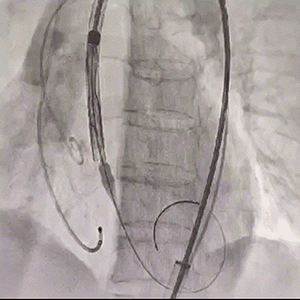

20mm球囊充分预扩

输送器顺畅过弓及跨瓣